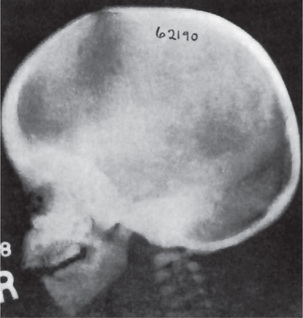

The radiographic hallmarks of osteogenesis imperfecta include osteopenia, bowing, angulation or deformity of the long bones, multiple fractures, and wormian bones (sutural bone) in the skull.

The bones in patients with osteogenesis imperfecta exhibit thin cortices, sometimes being composed of immature spongy bone, while the trabeculae of the cancellous bone are delicate and often show microfractures (Fig. 17-1). Osteoblastic activity appears retarded and imperfect, and for this reason the thickness of the long bones is deficient. The basic defect appears to lie in the organic matrix with failure of fetal collagen to be transformed into mature collagen. Qualitative defects (abnormal collagen I molecule) and quantitative defects (decrease in production of normal collagen I molecules) both exist. There is some evidence that the progressive intermolecular cross-linkage of adjacent collagen molecules, which is an essential characteristic of normal collagen maturation, is defective in this disease. Calcification proceeds normally. Defective microvascular system and decreased collagen fibril diameter have also been observed. The length of the long bones is usually normal unless multiple fractures have caused undue shortening.